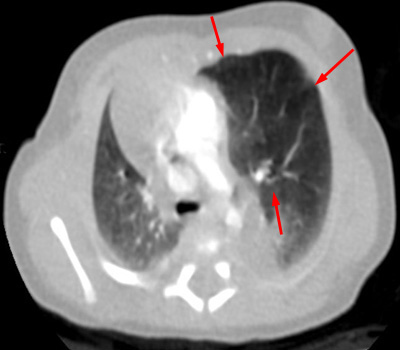

Chest CT on day 2 of life. The fluid has been absorbed and the left upper lobe is shown to be hyperinflated resulting in mass effect and shift of the mediastinum.